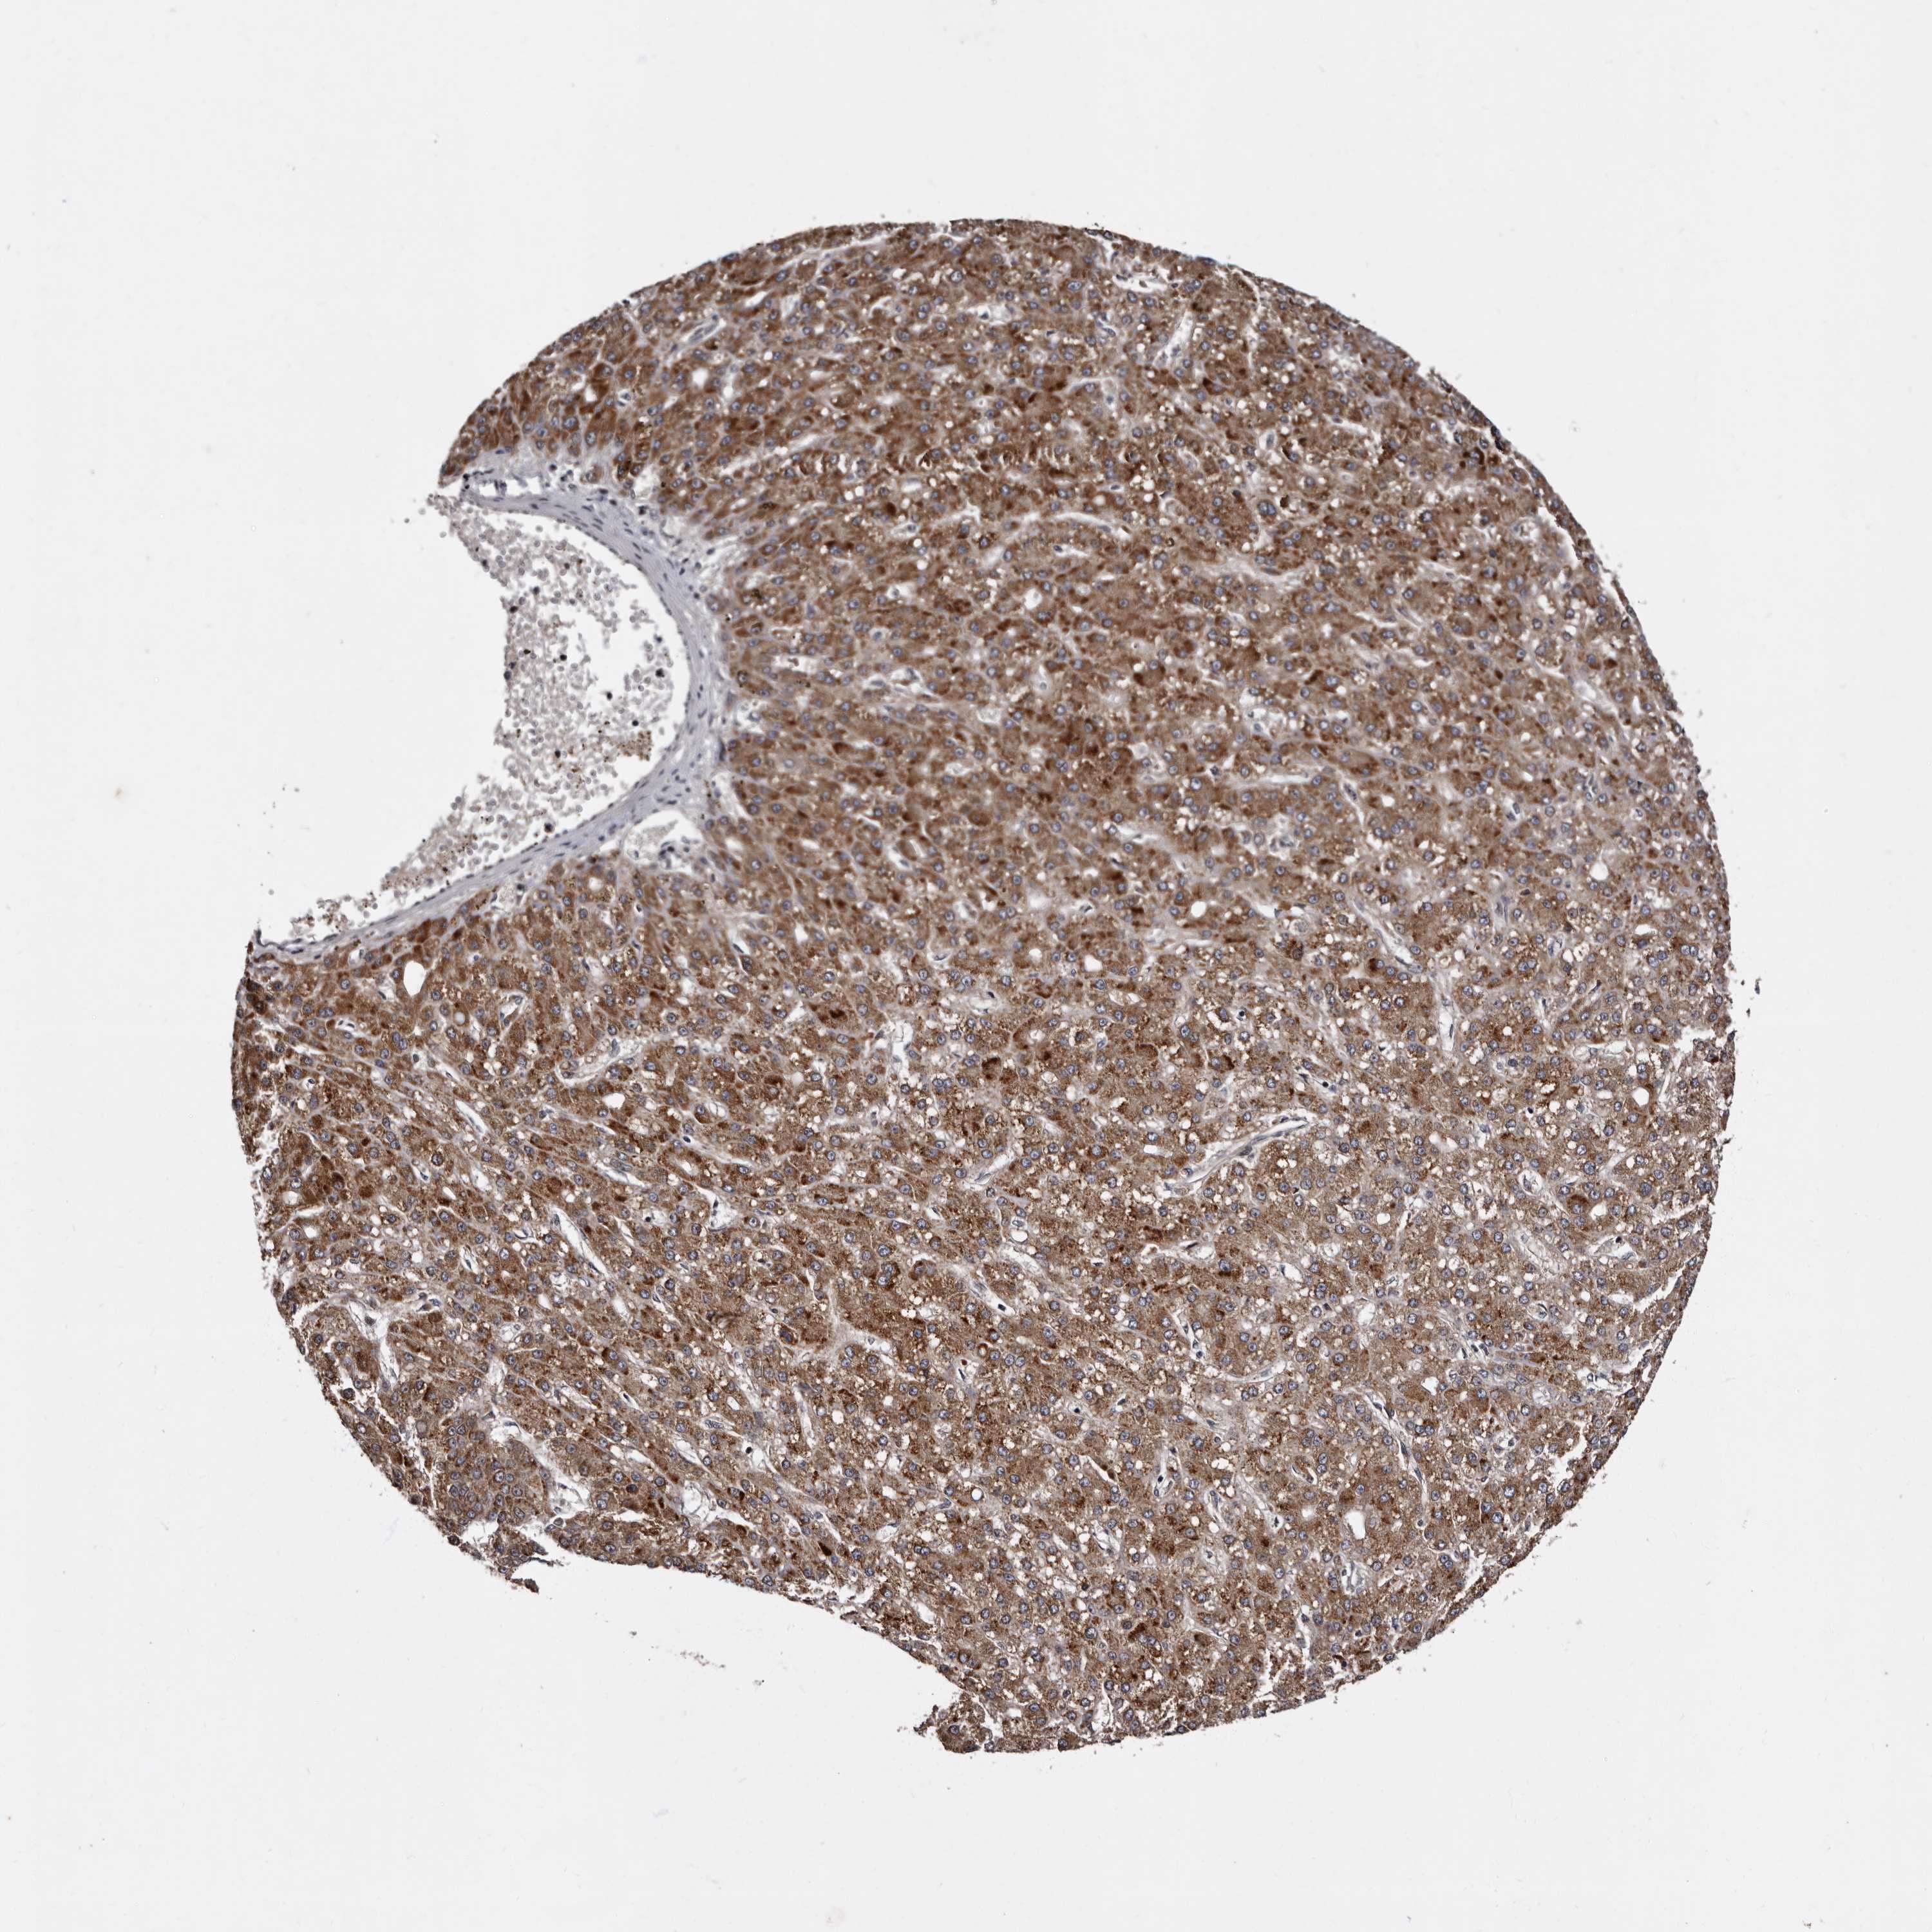

LIVER CANCER - Protein expressioni

A mouse-over function shows sample information and annotation data. Click on an image to view it in a full screen mode. Samples can be filtered based on level of antibody staining by selecting one or several of the following categories: high, medium, low and not detected. The assay and annotation is described here.

Note that samples used for immunohistochemistry by the Human Protein Atlas do not correspond to samples in the TCGA dataset.

Antibody stainingi

Antibody staining in the annotated cell types in the current human tissue is reported as not detected, low, medium, or high, based on conventional immunohistochemistry profiling in selected tissues. This score is based on the combination of the staining intensity and fraction of stained cells.

Each image is clickable and will lead to virtual microscopy that enables deeper exploration of all samples and also displays staining intensity scores, fraction scores and subcellular localization as well as patient and tissue information for each sample.

Antibody HPA025690

Staining

High

Medium

Low

Not detected

Intensity

Strong

Moderate

Weak

Negative

Quantity

>75%

75%-25%

<25%

None

Location

Nuclear

Cytoplasmic/membranous

Cytoplasmic/membranous,nuclear

Cholangiocarcinoma

Carcinoma, Hepatocellular, NOS